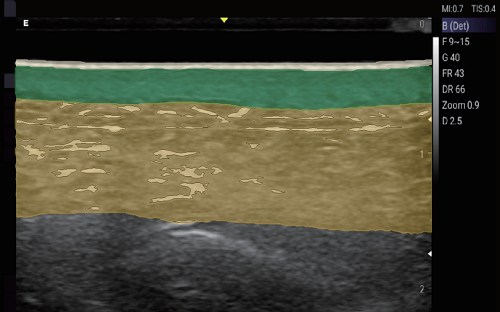

PAU2C aesthetic skin ultrasound device is portable and easy to use for aesthetic medicine. Handheld design allows aesthetic physicians to perform ultrasound whenever patients are in need. Aesthetic medicine ultrasound device works for medical beauty, clinic, hospitals, beauty salon. Our medical beauty ultrasound device that connects with WIFI without restrictions of wiring. Support windows, android, and IOS. Supported ultrasound exam presets for cosmetic medical services include fat factor, HA, PCL, CaHA, PLLA and PDLLA.

PAU2C is a game-changing ultrasound device for aesthetic and medical professionals, combining intuitive usability with advanced features to meet modern clinical and beauty workflow demands. Whether used to evaluate fat distribution, track filler efficacy, or assess tissue response, PAU2C delivers the precision, speed, and dependability professionals need for exceptional patient outcomes.

PAU2C redefines portability and user-friendliness in dermatological ultrasound. Its compact handheld design breaks bulky equipment constraints, enabling aesthetic physicians to provide on-demand skin ultrasound assessments during consultations, follow-ups, or on-site services. This flexibility makes it indispensable across settings: medical beauty clinics, private practices, hospitals, and high-end beauty salons—adapting seamlessly without compromising accuracy or performance.